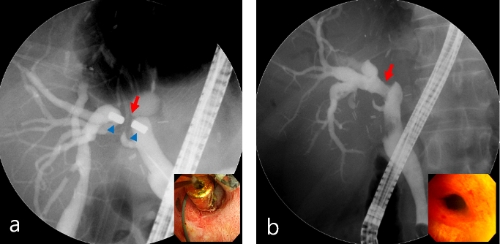

17일 강남세브란스에 따르면 자기압축문합술은 담즙관 협착시 자석이 지나갈 통로를 확보한 뒤 자석을 문합부와 그 맞은편에 위치토록 조정해 자석 사이에 위치한 조직이 지속적인 압력을 받아 괴사하면서 떨어지도록 하는 시술이다.

교수팀은 간이식 수술 79명과 기타 담도 수술 23명으로 담즙관 협착증세를 보였으나 수술이나 중재적 방사선술 등 통상적인 치료법 적용이 어려웠던 102명의 양성담관협착 환자를 대상으로 자기압축문합술을 시행한 결과, 95명(93%)의 환자의 막힌 담즙관을 뚫어 정상적인 기능을 회복시키는 성과를 거뒀다.